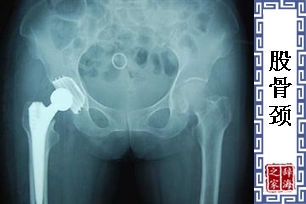

- 解剖学名词。股骨头和股骨干相接处称之为股骨颈。此触为股骨弯曲处,必需承受体重压力,以及弯曲倾斜度的影响。因有非常精细巧妙的固定骨组织。弯曲式杠杆的结构,须有正常合适的骨架排列。否则会因过重的体重而折断。生长发育期为保持骨细胞的柱状形式,股骨颈的结构会产生不断变化,这种变化正常与否是影响将来股骨颈形成法则的重要因素。